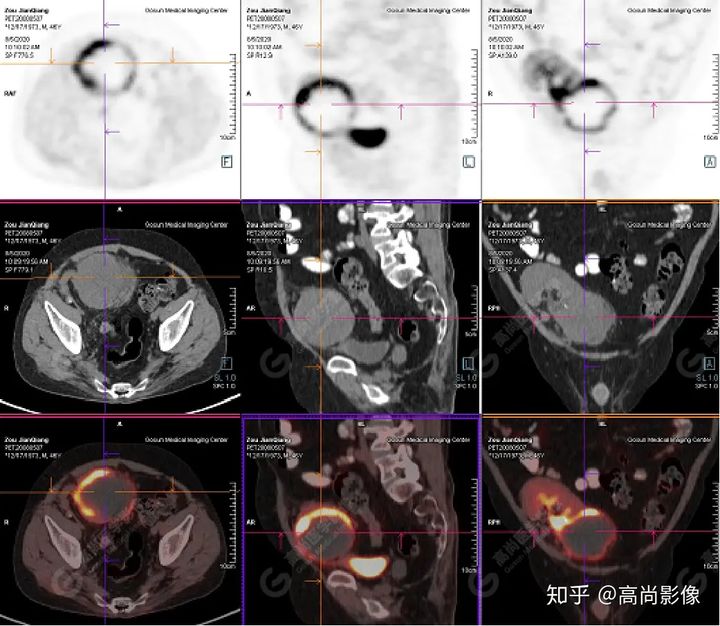

PET/CT檢查

↑移植腎下部等密度腫塊,代謝環(huán)狀增高,SUVmax13.4,中心代謝缺損